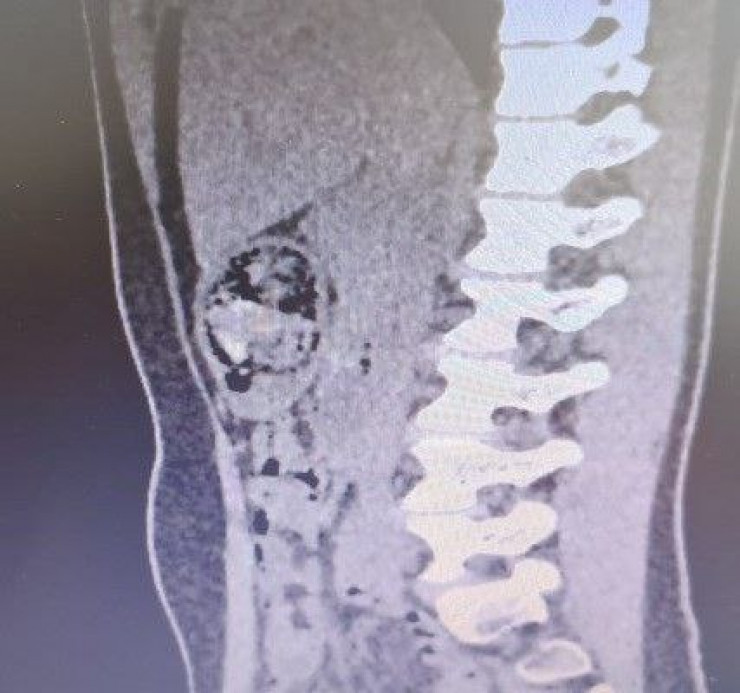

В ходе оперативного вмешательства из желудка пациентки было изъято около 1,2 килограмма инородного тела – трихобезоара (волосяной ком). Операцию провела бригада специалистов: заведующий хирургическим отделением Эльбрус Салпагаров, заведующий операционным отделением Канат Дуйсебаев и анестезиолог Бахтияр Баялиев. Сейчас девочка идет на поправку.